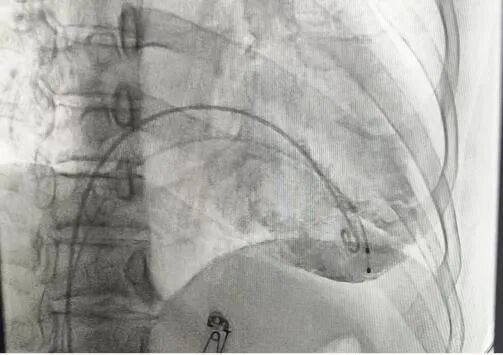

手术过程部分展示

左前45°造影贴靠间隔

后撤保护套筒并释放调弯,保持合适张力,避免前向压力

开始旋入AveirVR